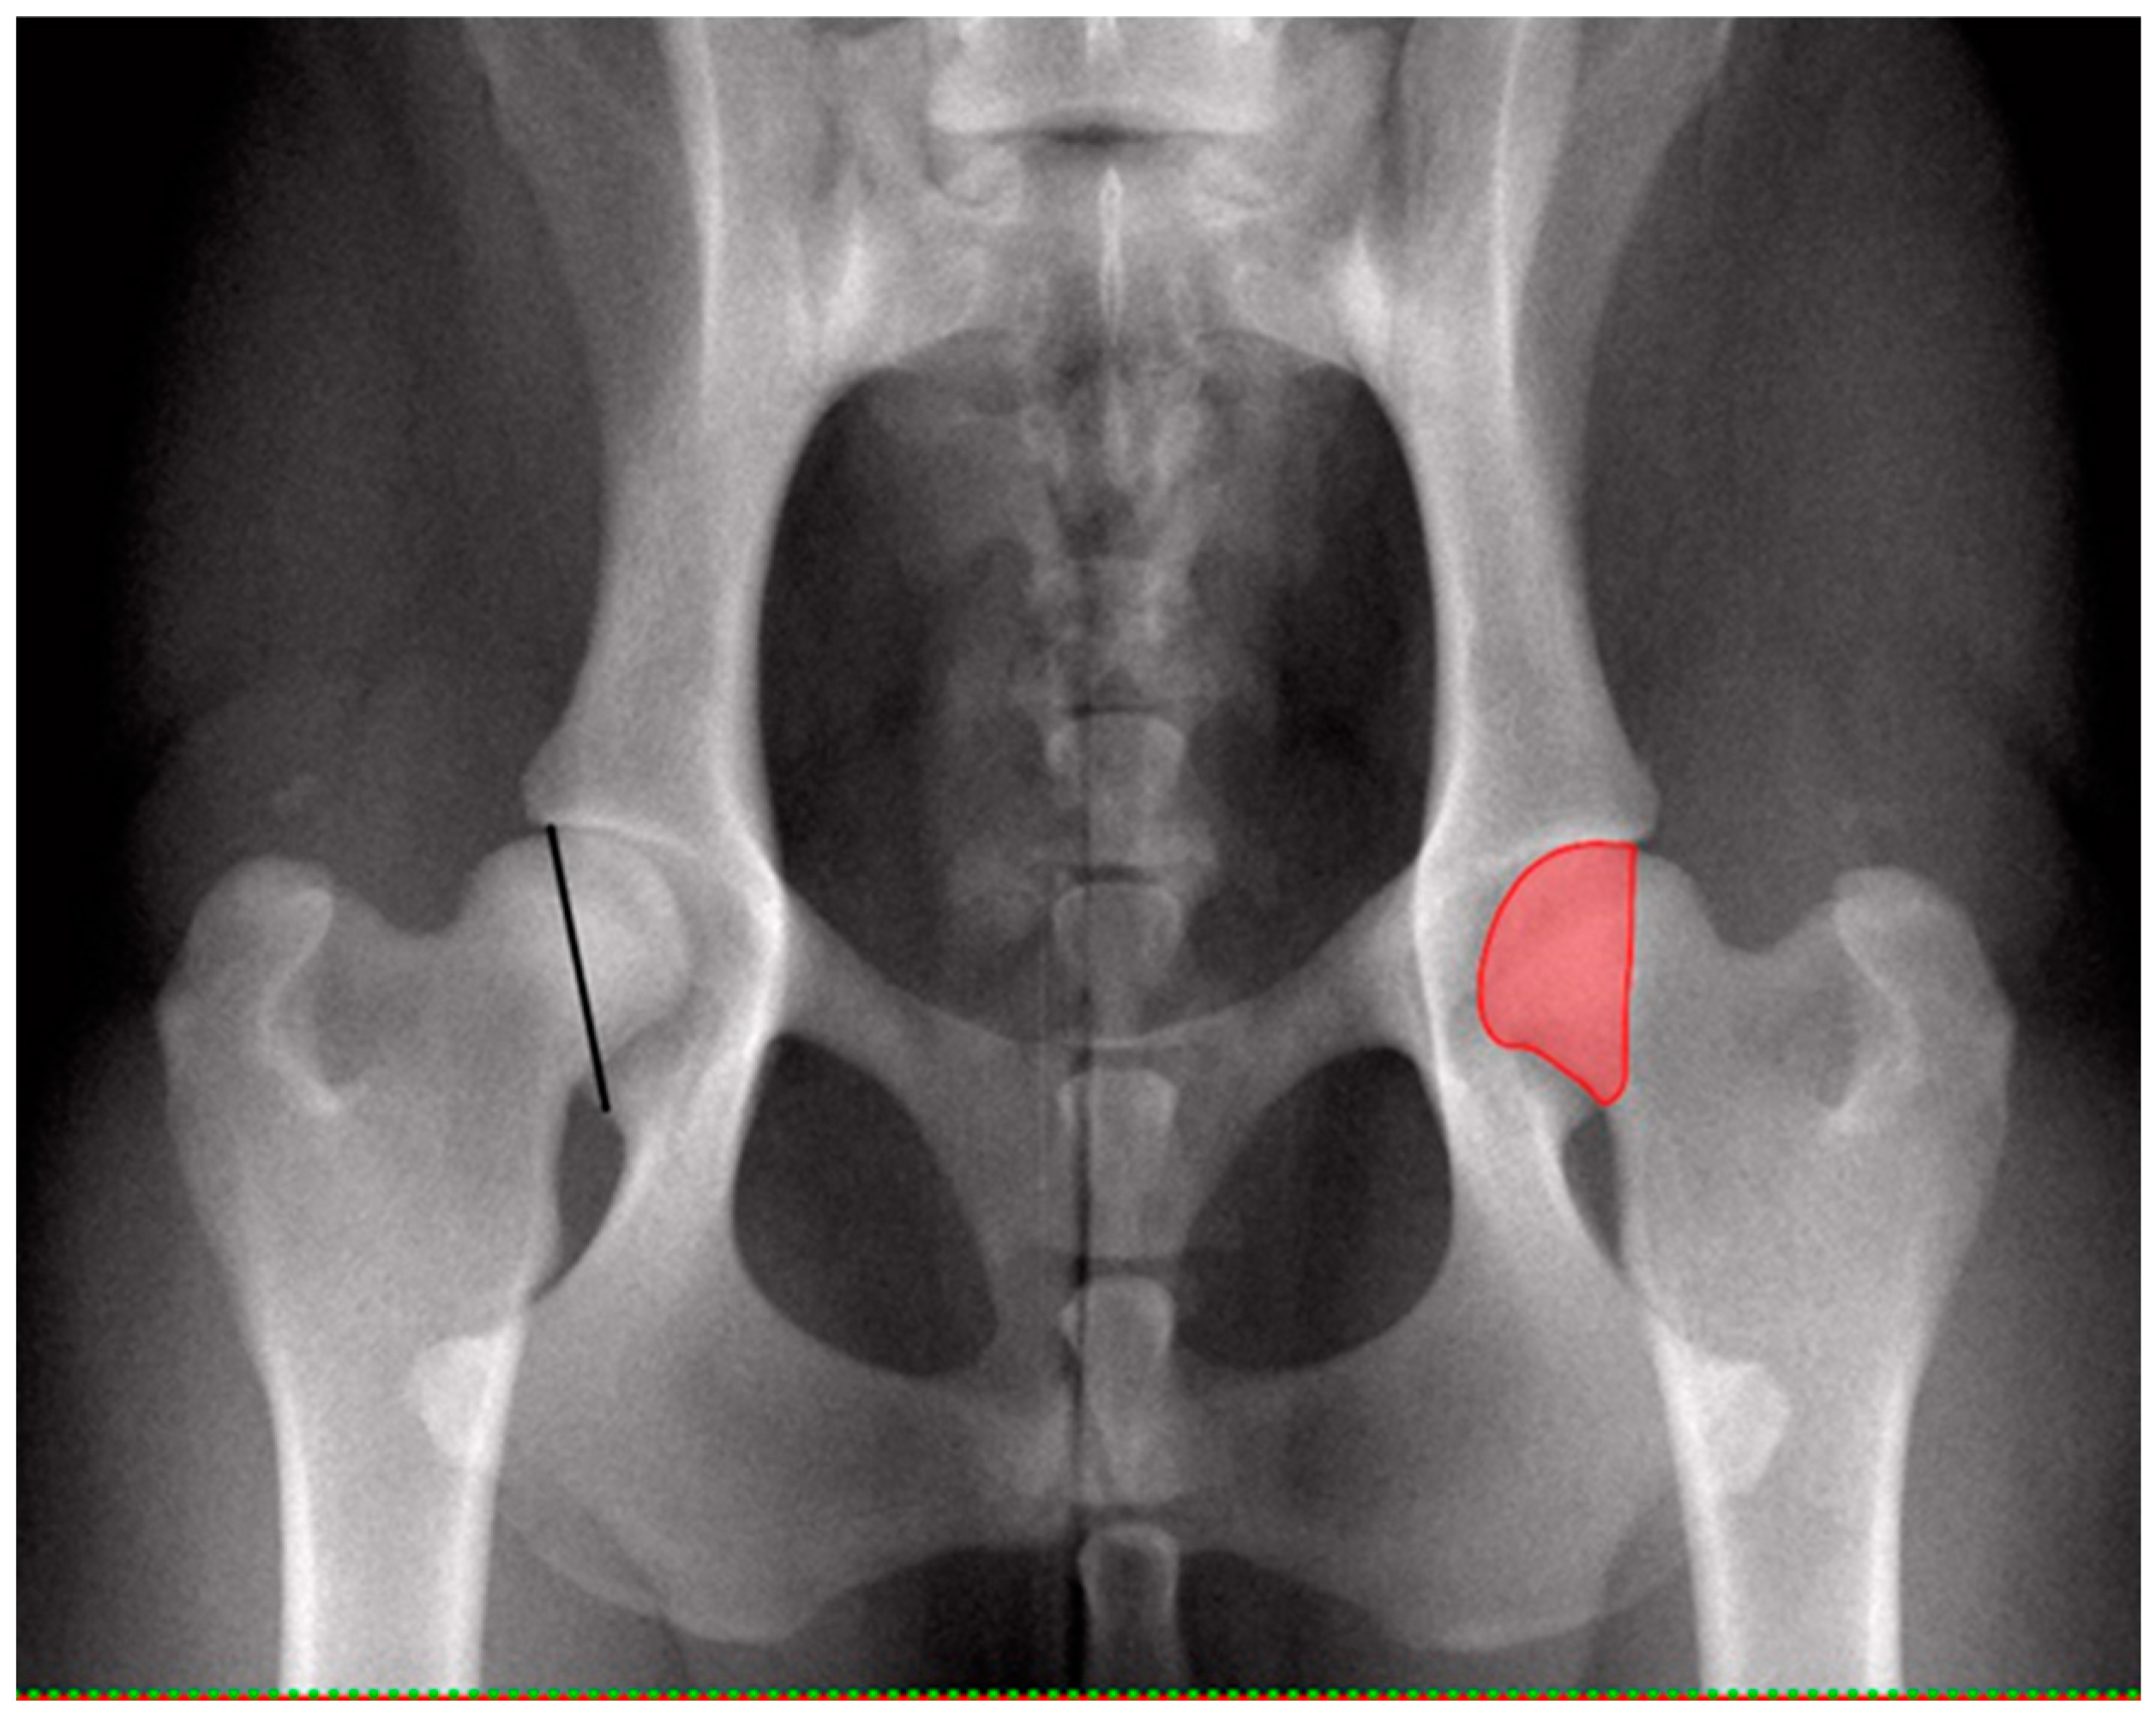

Radiographs were taken with digital radiography in symmetrical ventrodorsal projection with extended, parallel femora and patellae in the middle of the femoral condyles while dogs were under general anesthesia with muscle relaxation achieved by a routine injectable anesthetic protocol. Hip joints were evaluated for dysplasia based on FCI criteria from A to E [3,4,5] for every hip joint separately by blinded authorized investigators (DSI, BT). DICOM reader software (Version V3.3.6, Horos, for Apple Macintosh) was utilized to determine femoral head area (FHA) and percentage femoral coverage by the acetabulum (CFH). For this purpose, measurements were performed by a trained postgraduate student (MP) blinded to dysplasia scores. The diameter, circumference and FHA were determined by drawing the best fitting circle around the femoral head using a circle template with a line of least thickness. The overlap of FHA and dorsal acetabular roof (surface femoral coverage) was determined by drawing a line along the dorsal acetabular rim connecting to the circle of the femoral head cranially and caudally. Area calculations were performed by the software and recorded in square centimeters. Percentage CFH was calculated manually by dividing FHA superimposed by the acetabulum by the total FHA and multiplied by 100 [6,8,9]. Each individual hip score was related to FHA and CFH. Comparisons were made between dysplasia-free and dysplastic hips. Dysplasia-free was defined as hips having a score A, while dysplastic was defined as having mild, moderate or severe CHD (score C–E). Additionally, the shortest distance between the cranio-lateral edge and the caudo-lateral edge of the acetabulum was measured with the distance tool of the DICOM reader software and related to the corresponding FHA (Figure 1).

Figure 1. Ventrodorsal pelvic radiograph of normal coxofemoral joints (left) indicating the cranio-caudal distance of the dorsal acetabular rim (CrCdAR), the shortest distance (black line) between the craniolateral edge and the caudolateral edge of the acetabulum and (right) surface coverage of femoral head (CFH, red area).